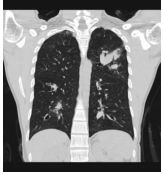

2. A 27-year-old woman had productive cough for one month.